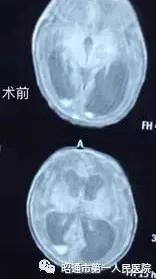

目前已术后近2月,该宝宝各项生命体征平稳,生长发育指标在正常标准差之间,复查头颅MRI已基本正常,宝宝无神经系统的异常表现。

术前术后头颅MRI结果对比如下: